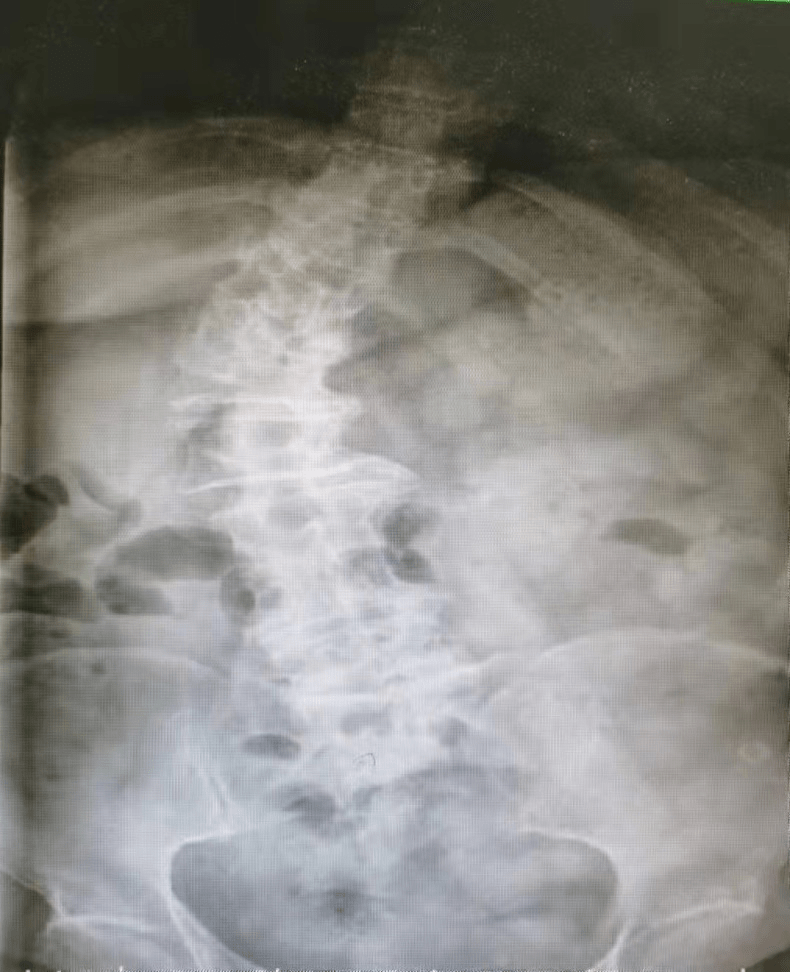

第一 , 李阿姨从8岁起就发现腰椎有先天性脊柱侧弯 , 那时候年轻 , 也没觉得有什么问题 。 等到20来岁以后 , 这脊柱侧弯的症状就越来越明显:因为脊柱畸形 , 右边后背鼓起一个大包 , 整个人身体歪向左侧 , 走路一扭一拐的 。

那么李阿姨的腰椎到底弯到了什么程度呢?大家可以看一下:

第二 , 光是脊柱侧弯导致走路不好看也就算了 , 最关键是脊柱侧弯导致严重的椎间盘突出、骨质增生 , 身体形态改变导致髋关节、膝关节受力改变 , 慢慢的都出现关节变形 , 腰疼、髋关节疼痛、膝盖痛的毛病一个跟着一个都来了 。

其中最难熬的就是腰疼 , 腰椎是人体负责承上启下的主要结构 , 其中相关的血管、神经、肌肉不计其数 , 李阿姨的腰椎侧弯非常严重 , 还是扭转弯的那种 , 就跟拧了个麻花似的 , 可以想象里面的神经都被压成什么样子了 。